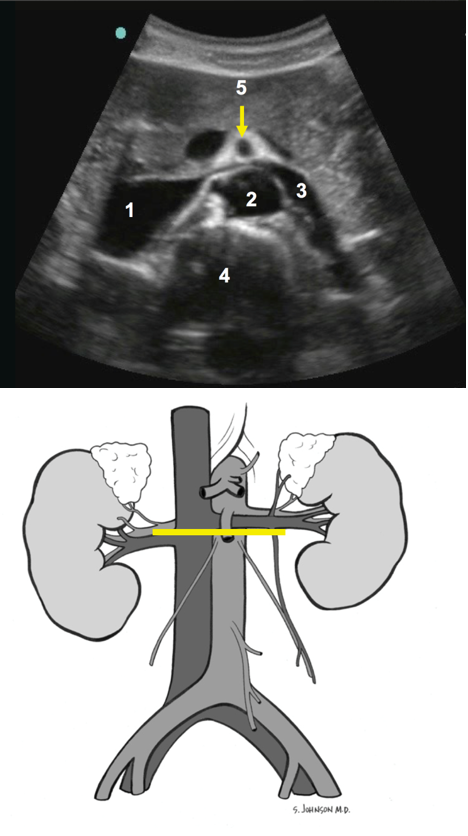

1. Vena cava inferior (VCI)

2. Aorta (Ao)

3. Linke Vena renalis

4. Wirbelsäule

5. Arteria mesenterica superior (AMS)